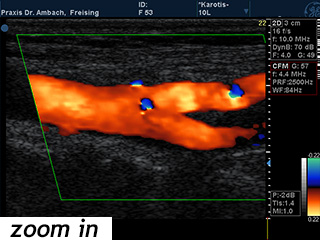

Gefäßdoppler

Mit Hilfe des Ultraschalls können unter Anwendung der Doppleruntersuchung und der Farbcodierung des Blutflusses die verschiedenen Gefäße des Körpers untersucht werden: Zum Beispiel die Halsschlagadern (Carotiden), die Bauchschlagader (Aorta abdominalis), die Nierenarterien, die Beingefäße etc. Die Darstellung der Nierengefäße dient der Abklärung eines hohen Blutdrucks. Mit der Untersuchung der hirnversorgenden Gefäße können Verengungen oder Verkalkungen beurteilt werden, sie kann außerdem auch Hinweise auf eine möglicherweise gleichzeitig bestehende Herzerkrankung geben.